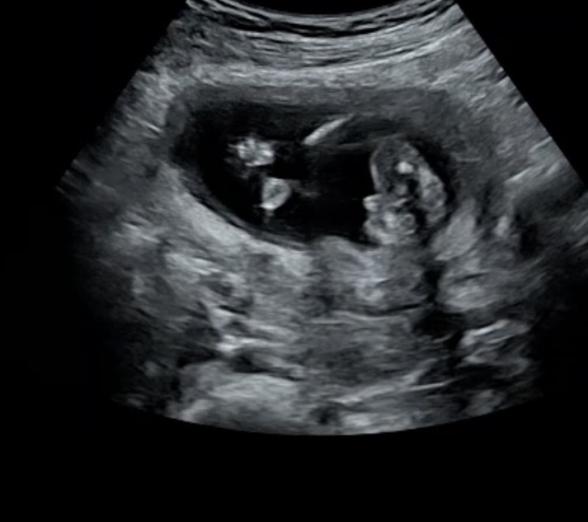

15週1日で受診した時のお話です

担当の先生からはまだハッキリしないけど男の子ぽいかなーと言われました。

エコー写真はおしりを下からみた角度になります。わたしは15週でこれくらいはっきり見えてたら確実なのかなと思いました!

お尻を下から見た角度のエコー写真だということなのですが、はっきりとお股のあたりが写っている様子には見えず、男の子のシンボルとして、見て良いのかどうか疑問に思いました。

性別を確認するのであれば、もう少しエコーで様子を見てみたいなと思いました。